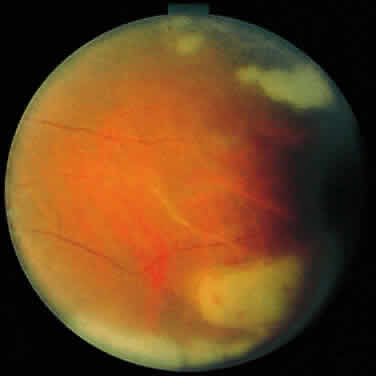

ARN is characterized by a retinal vasculitis affecting both the arteries and veins in the fundus, which is manifested by sheathing of the larger vessels (Fig. 2).7–10,16 Initially, patchy areas of peripheral retinal whitening (“thumbprint lesions”) representing full-thickness retinal necrosis are present or develop shortly after the vasculitis (Fig. 3). During a course that may span days or weeks, these patches coalesce into geographic areas (Fig. 4A). The entire peripheral retina (360 degrees) may be involved, or, more commonly, there are several noncontiguous patches of necrosis, each covering from a half to three clock hours (Figs. 5 and 6). The posterior segment lesions may not be detected without examination of the peripheral retina.

As the infection progresses, the leading edge of confluent retinal whitening advances toward the posterior pole (Fig. 7A). The retinitis may not progress posteriorly to the vascular arcades, sparing the macula and central vision. It is hypothesized that the retinal necrosis in ARN results from the combined effect of intracellular viral replication with subsequent cell death and vascular occlusion secondary to acute vasculitis. In some patients, the retinal vasculitic component may be much more prominent than the retinal necrosis.7 Optic disc swelling, either hyperemic or pallid, is a common feature of the ARN syndrome.1 Perivascular hemorrhages may be present (Fig. 8); however, widespread areas of retinal hemorrhage are atypical. Retinal vascular occlusion, often involving the arteries, can occur at any point during the clinical course. Without treatment, the inflammatory component of ARN typically burns out in 6 to 12 weeks, leaving behind a thin atrophic retina with associated pigmentary changes.10